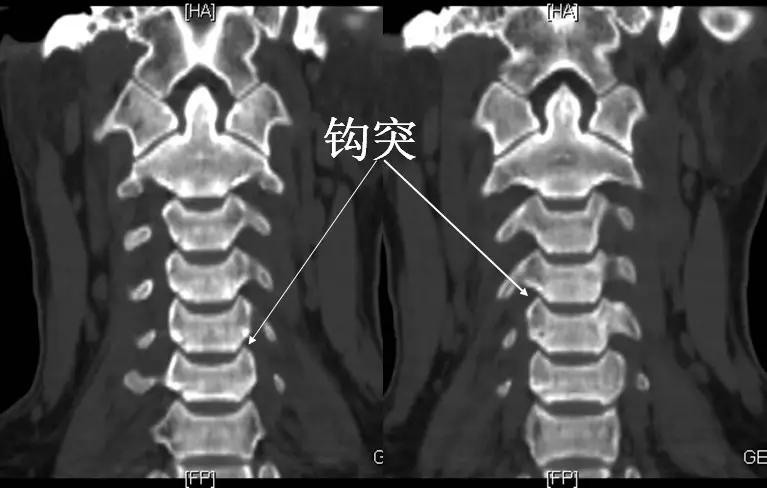

颈椎钩突:第3~7颈椎体上缘两侧斜向外上方的致密小突起,与上位椎体后外下缘构成钩椎关节,又称Luschka关节。

钩椎关节

在枢椎至第一胸椎之间,在椎体上面的侧方,向上隆起形成钩突,与相邻椎体下面侧方的斜坡构成关节即钩椎关节。

钩椎关节具有类似滑膜关节的结构,起限制颈椎侧方滑动的作用。

此关节和相邻的椎体部分构成椎间孔的前壁,而其侧方与动脉毗邻,发生骨刺时,向后方能挤压椎间孔内的组织结构,向侧方能影响椎动脉和其周围的交感神经。

钩椎关节(Luschka关节)它的增生可导致颈椎病。